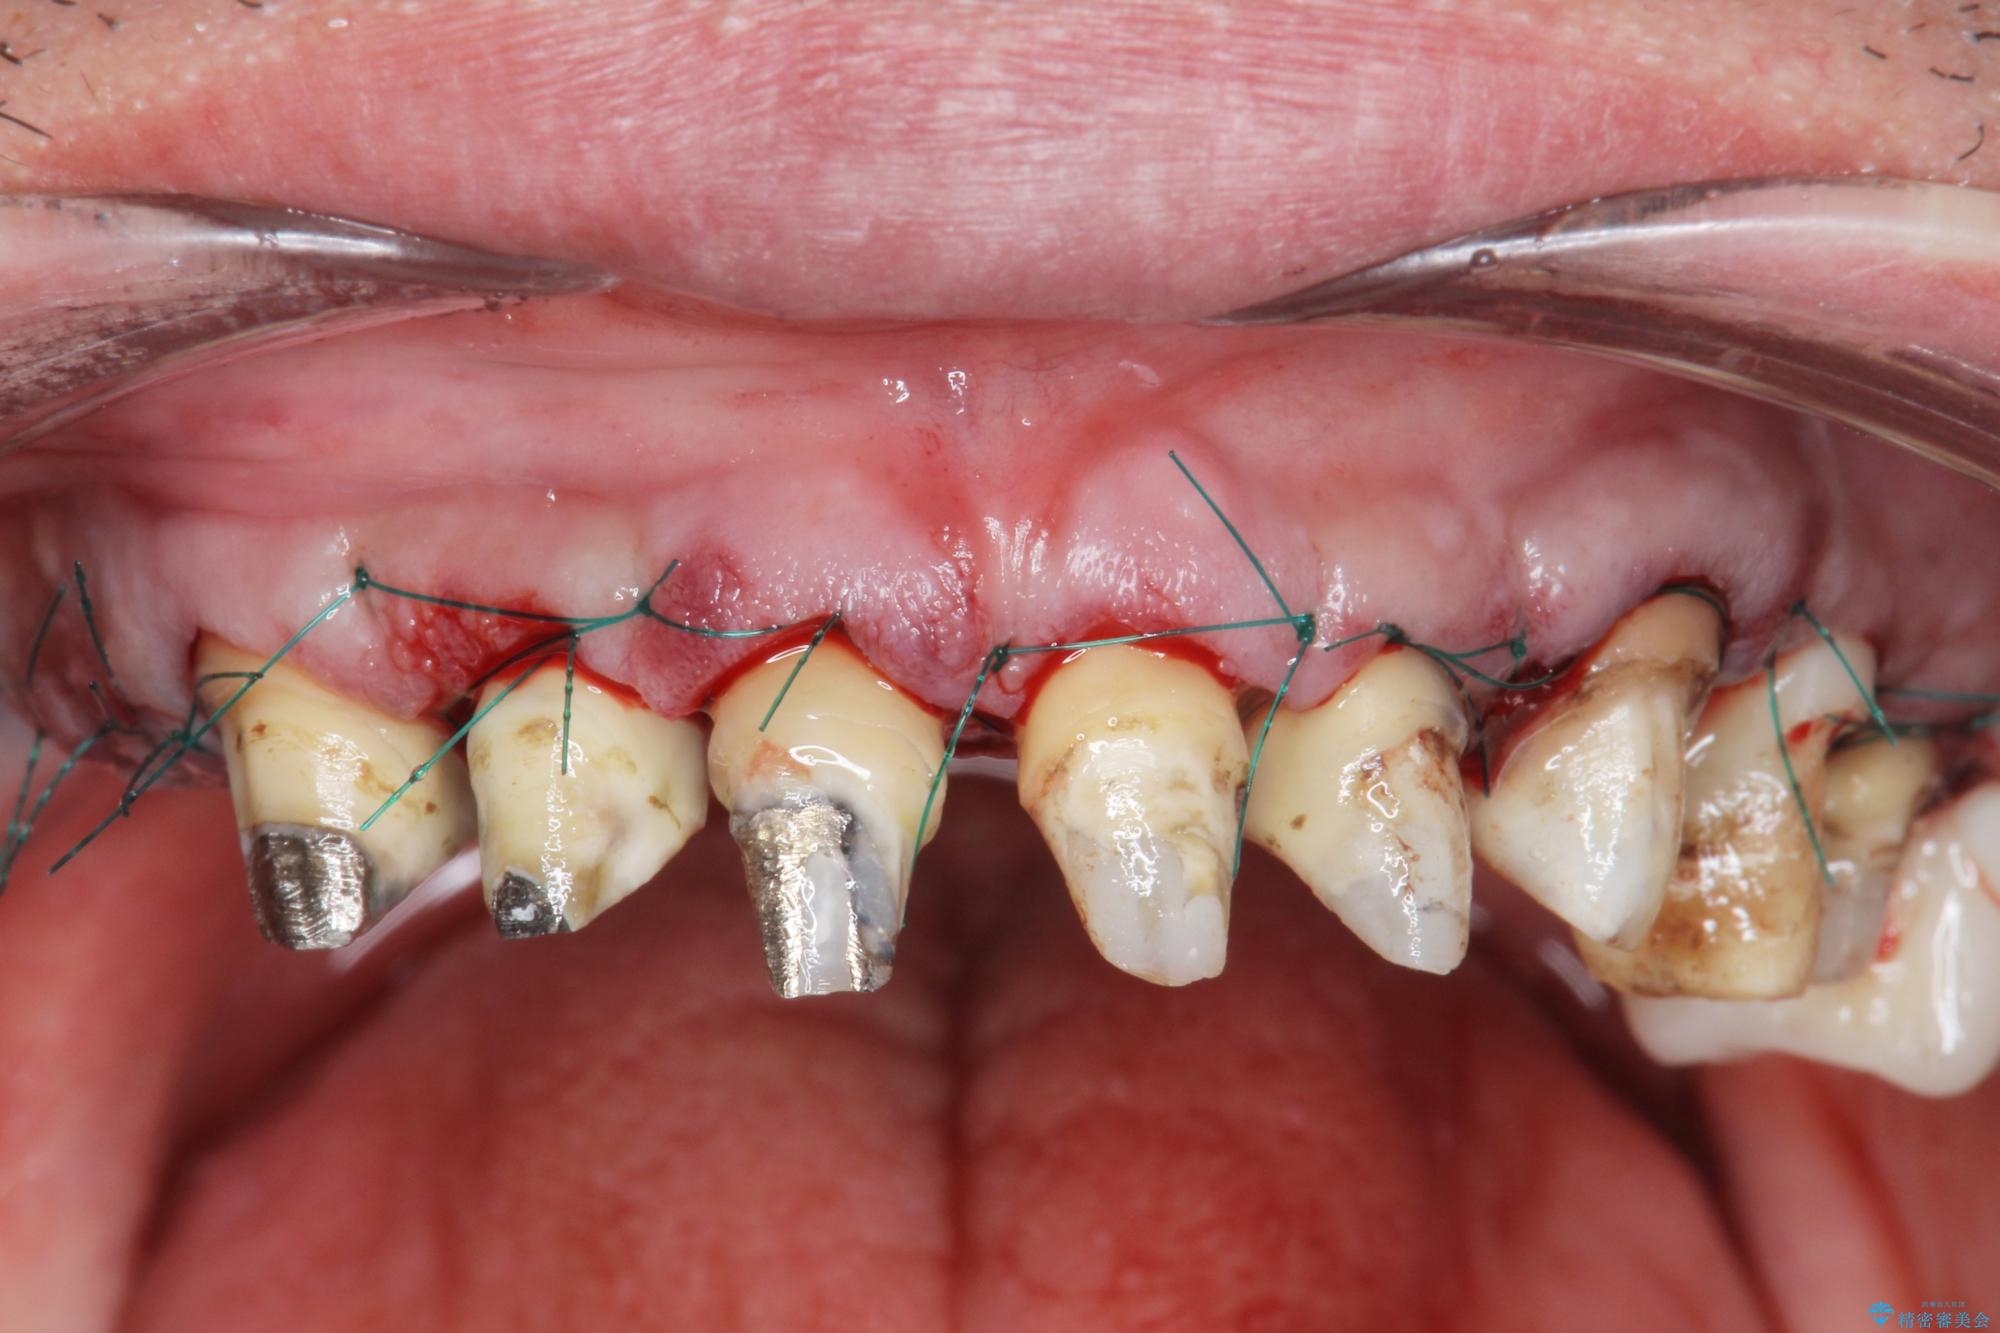

[ 歯周外科手術 ] セラミック治療後の歯ぐきの違和感

歯周組織検査を行うと歯ぐきからは容易に出血し、X線検査より歯とセラミッククラウンの適合が悪い(ピッタリと合っていない)状態が示唆され、歯ぐきの炎症を惹起している状態でした。

セラミッククラウンを除去し仮歯を装着し、歯周外科手術を行い歯ぐきの状態を改善したのち、適合の良いセラミッククラウンを再作製をする治療計画としました。

外科処置の注意事項(リスク・副作用など)

- 外科手術のため、術後に出血、痛みや腫れ、違和感を伴います